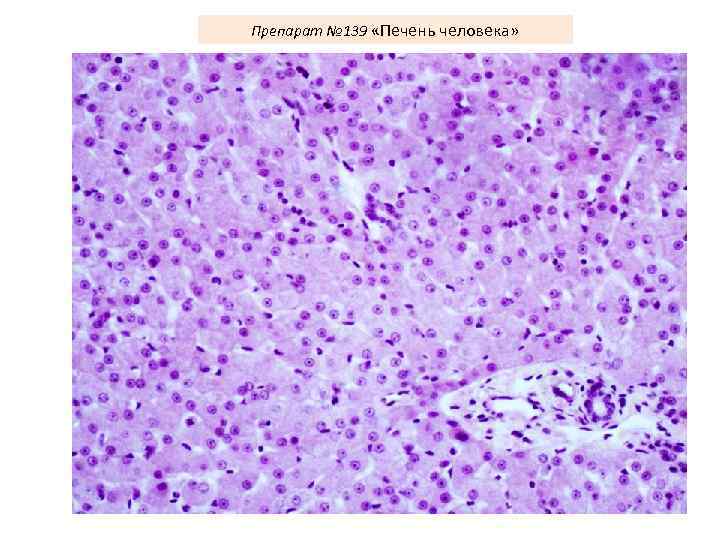

Препарат № 139 «Печень человека»

Препарат № 139 «Печень человека»

Препарат № 139 «Печень человека»